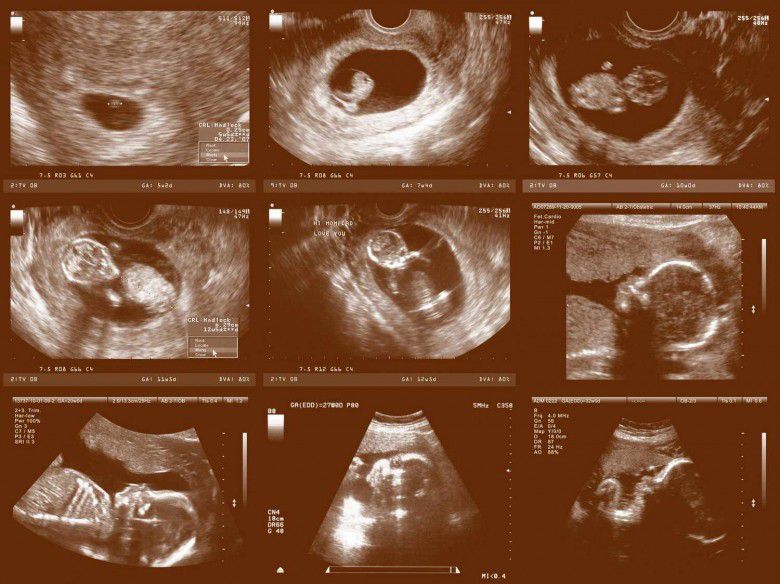

Perkembangan bayi dalam kandungan (parents.com)